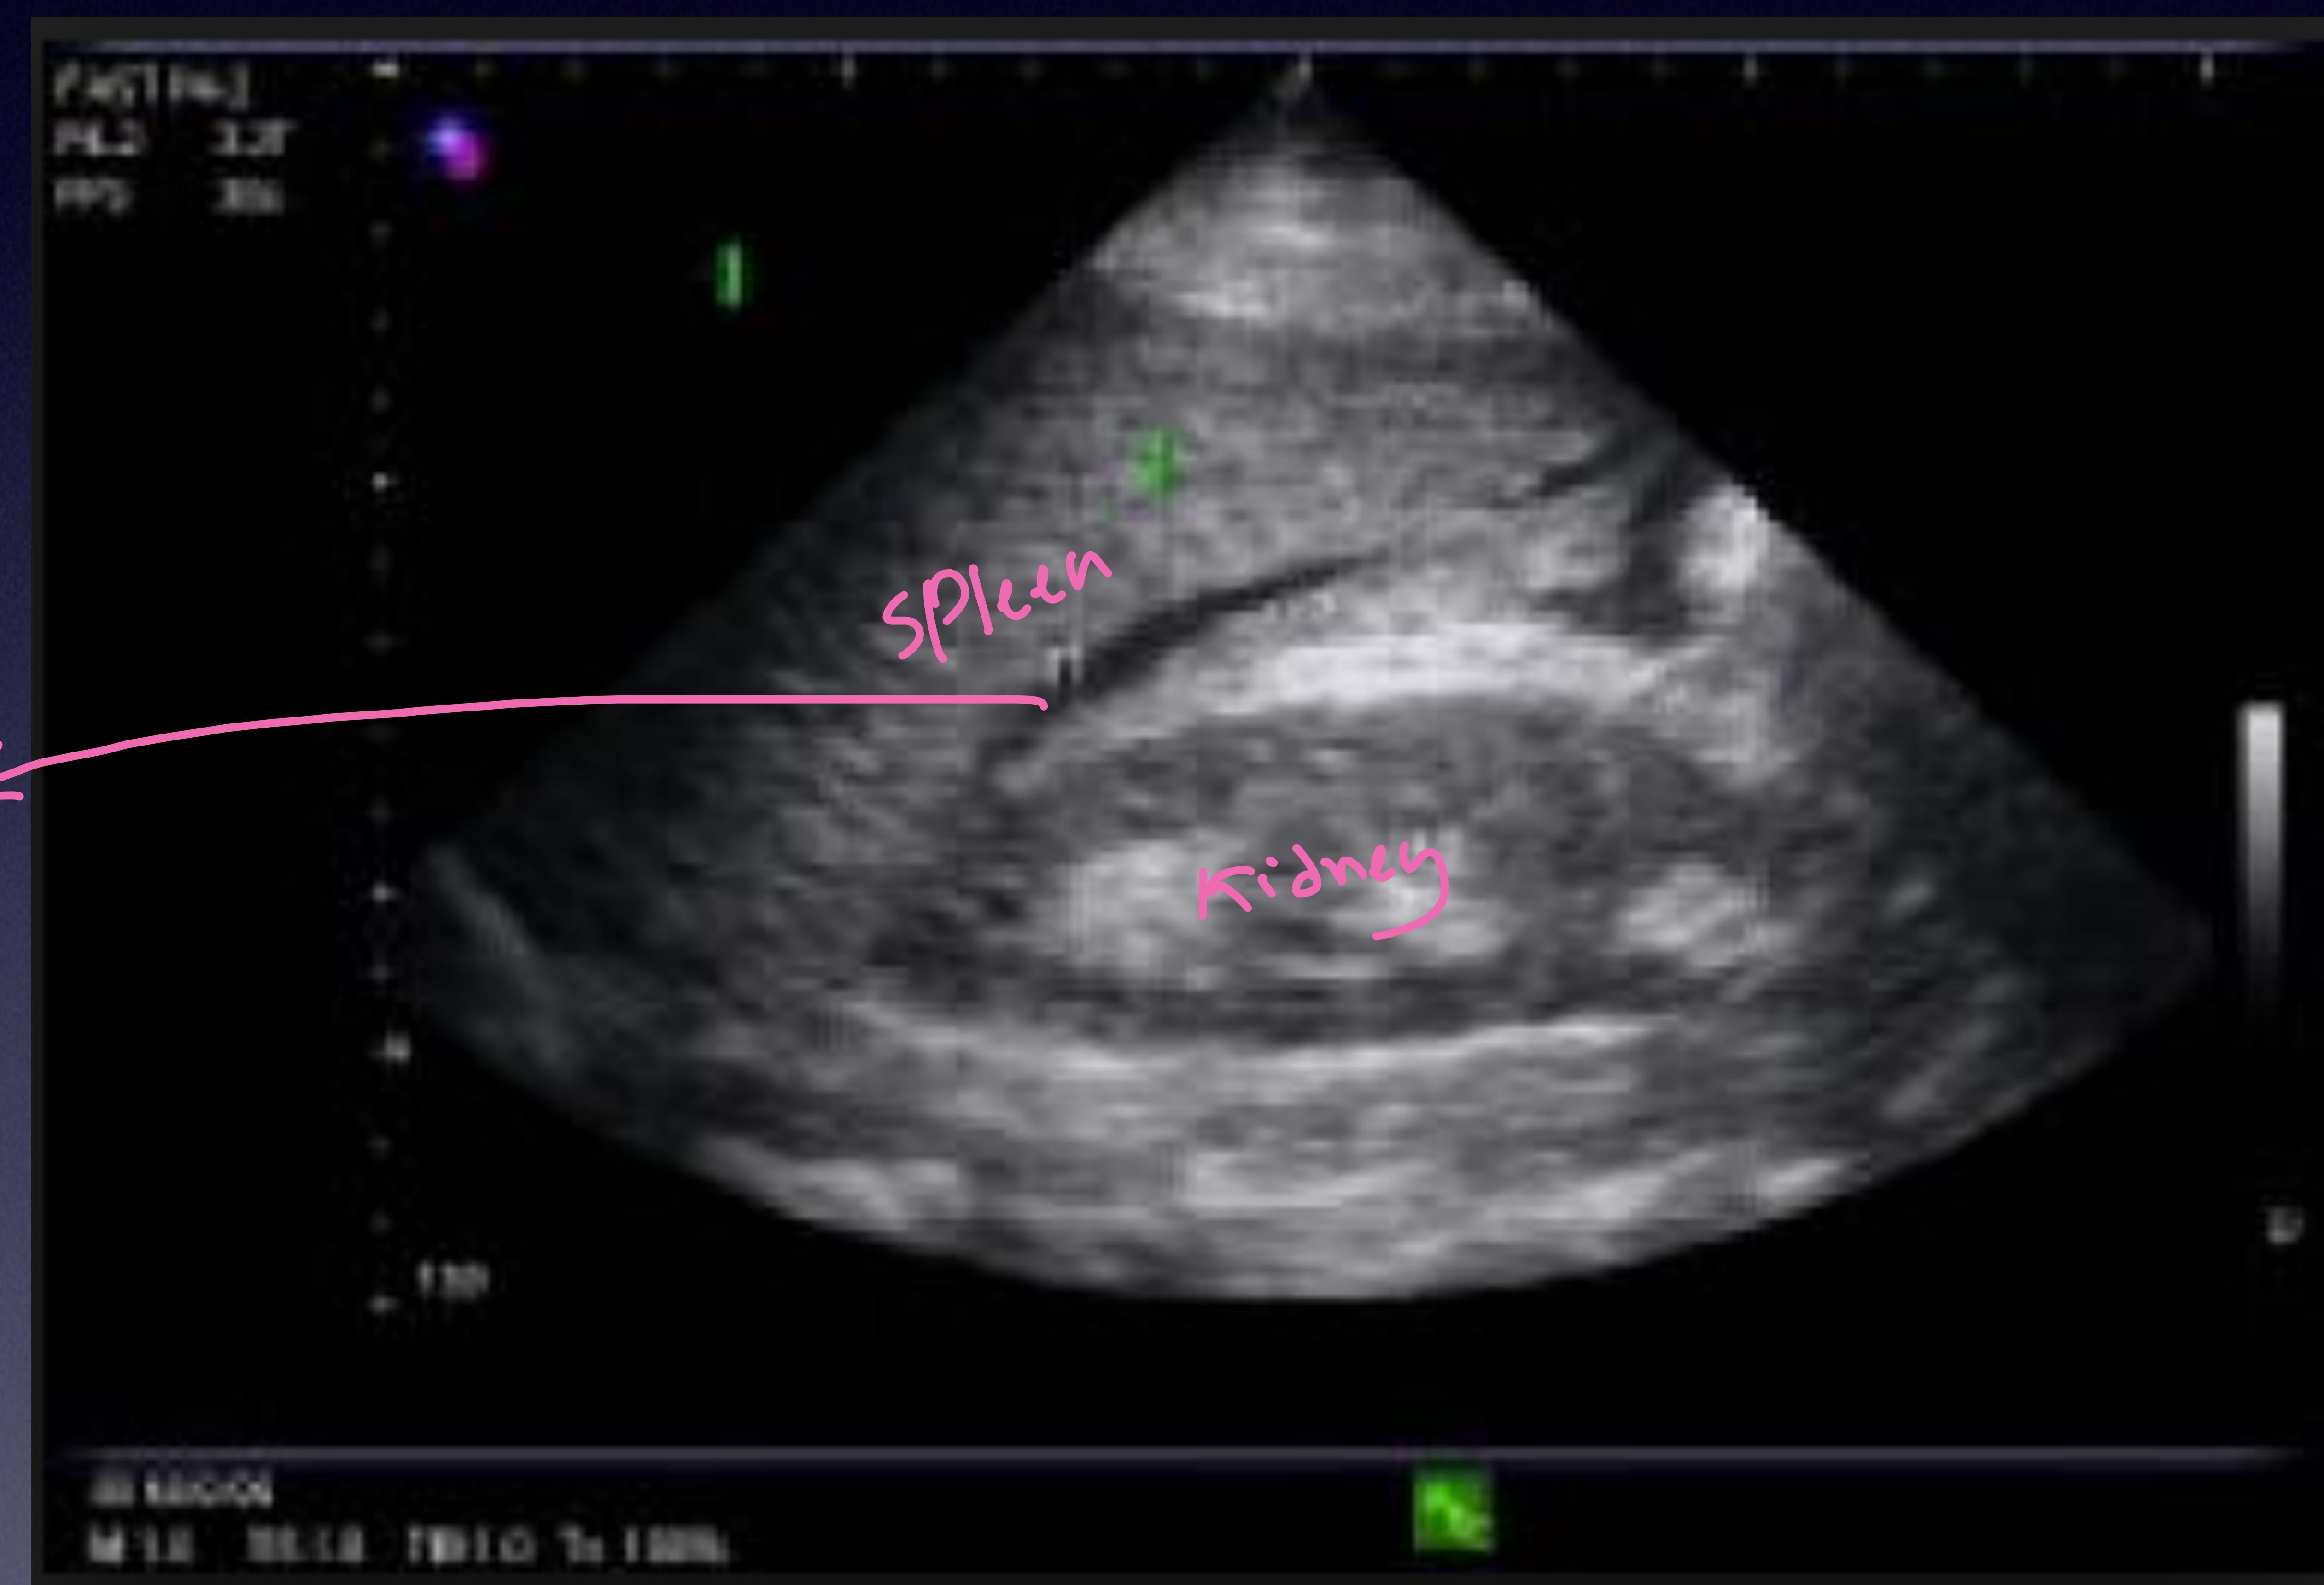

LUQ Scan (Splenorenal)

Spleen and Kidney interface.

Splenorenal view.

Spleen, Kidney, and Blood.